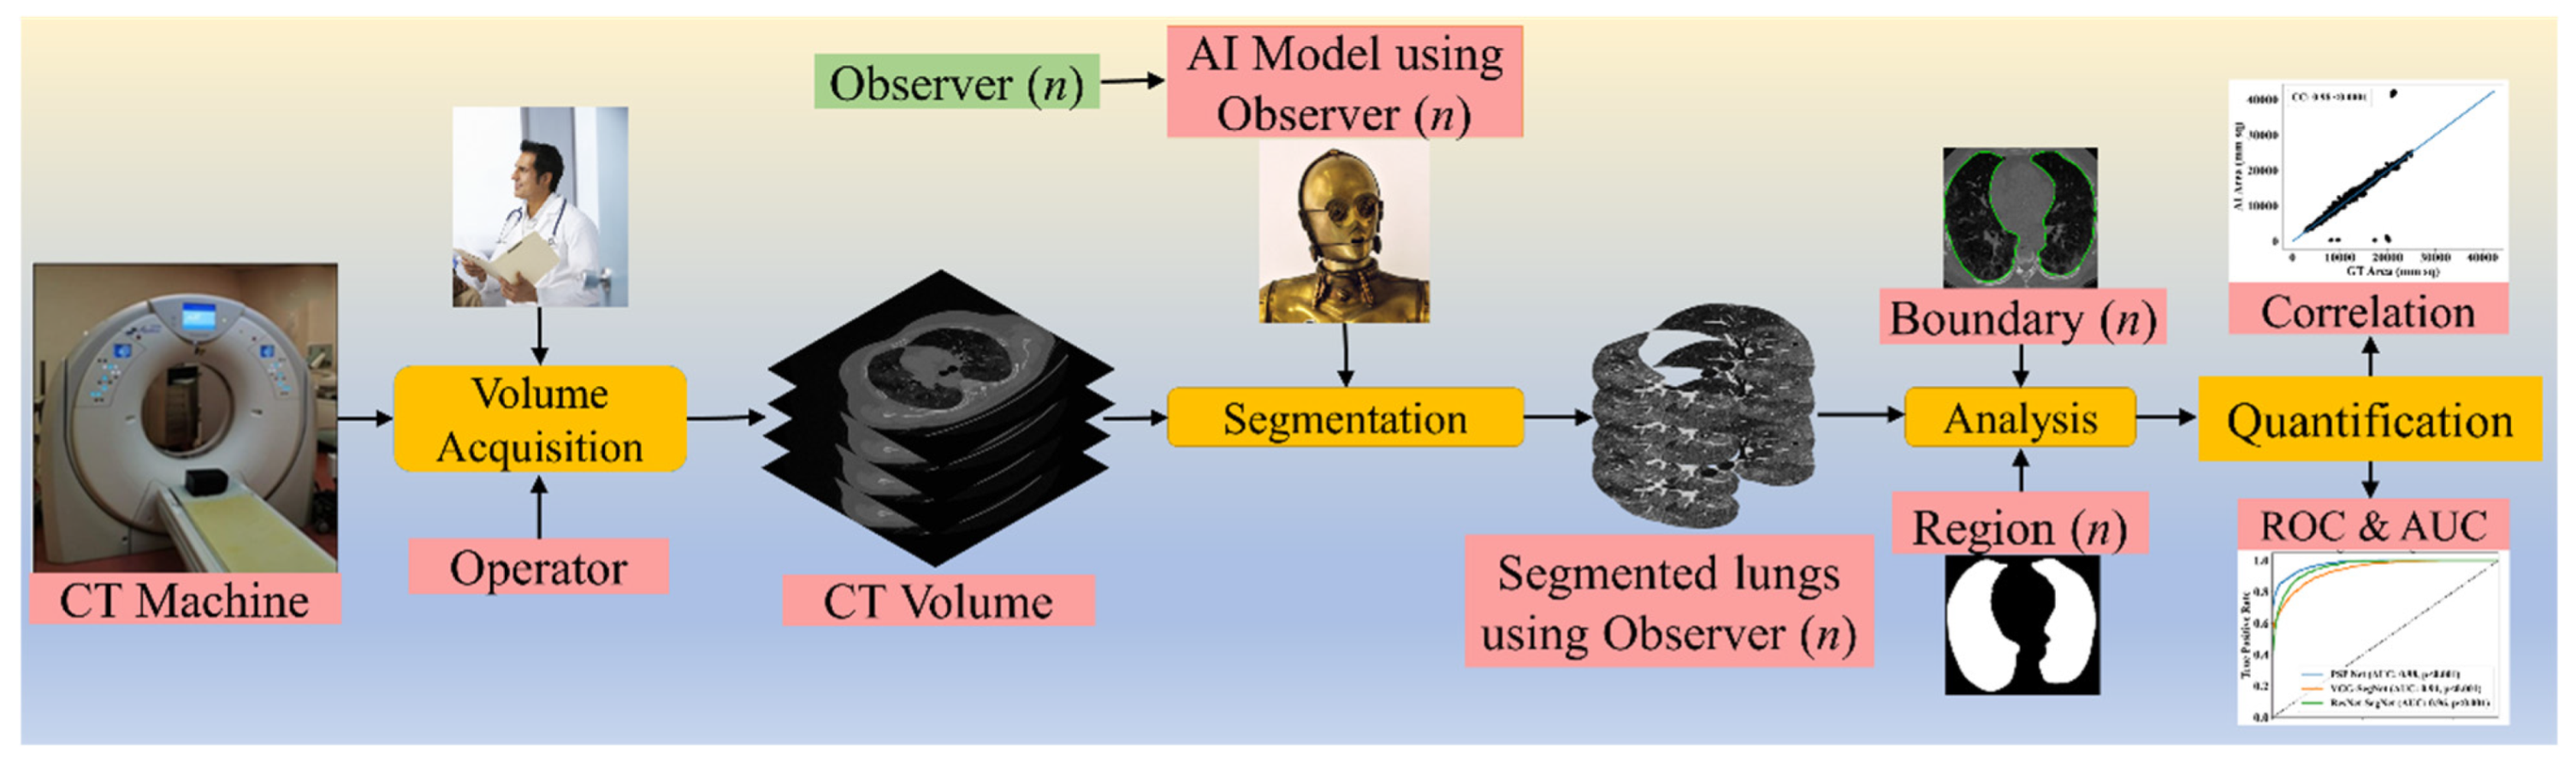

2. Methodology

2.1. Patient Demographics, Image Acquisition, and Data Preparation

2.1.3. Data Preparation

2.2. Architecture

3. Experimental Protocol

3.1. Accuracy Estimation of AI Models Using Cross-Validation